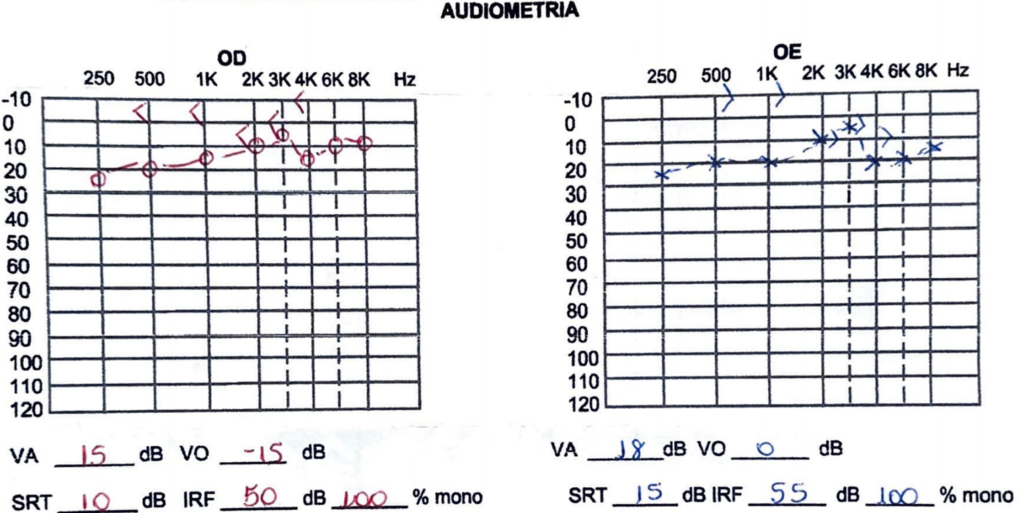

A audiometria mostra um diferencial aéreo – ósseo dentro da faixa de normalidade.

No exame de ressonância magnética da mastoide foi observado a presença de deiscência do canal semicircular superior bilateralmente. Na deiscência (Sindrome da Terceira Janela), costumamos observar esse diferencial aéreo-ósseo. Isso ocorre, porque parte da energia sonora transmitida através da janela oval “se perde” pela deiscência (via aérea), o que já não ocorre na via óssea.